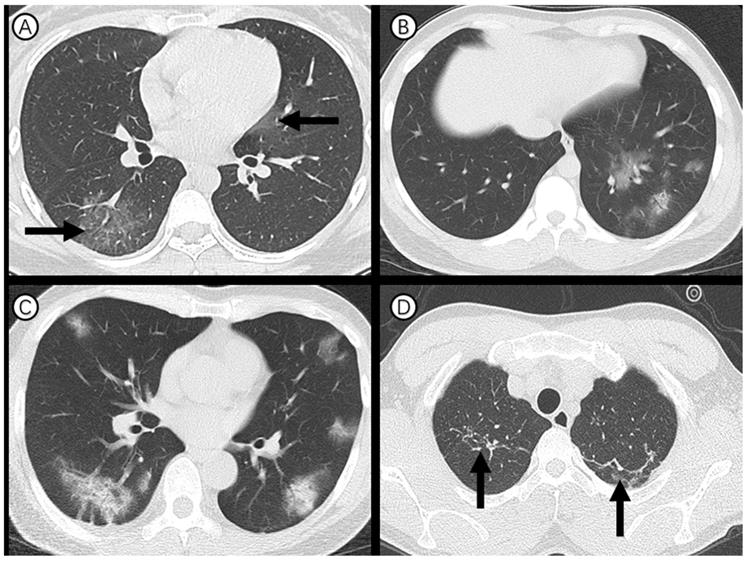

Axial thin-section CT scans in medical staff infected with SARS-CoV-2. (A) 27-year-old woman: bilateral, peripheral ground-glass opacity in the right lower lobe and left upper lobe (arrow). (B) 27-year-old man: unilateral, multiple and perbronchovasular ground-glass opacity associated with air bronchograms in the left lower lobe. (C) 55-year-old man: bilateral, peripheral ground-glass opacity mixed consolidation pattern. (D) 28-year-old man: bilateral and linear atelectasis in the right and left upper lobes (arrow), regarded as chronic lung lesion with lack of changes on serial CT examinations.

Ninety-one (90%) of 101 cases showed abnormal chest CT (Figure 2). Sixty-three (62%) had bilateral lung involvement (Figure 2, A and C). The right lower lobe (68 %) and left lower lobe (70%) were the most common involved lobes. Ground glass opacity was the predominant abnormality on chest CT (Figure 2, A and B) and observed in 48 cases (48%). Subpleural distribution was predominant distribution pattern of the ground glass opacity as identified in 78 cases (77%) (Figure 2, C). Adjacent pleura thickening, nodules, emphysema, pleural effusion and lymphadenopathy were relatively rare. CT scans also found that 23 (23%) of medical staff had one or more chronic lung lesions with unchanged appearance on serial CT examinations (Figure 2, D).